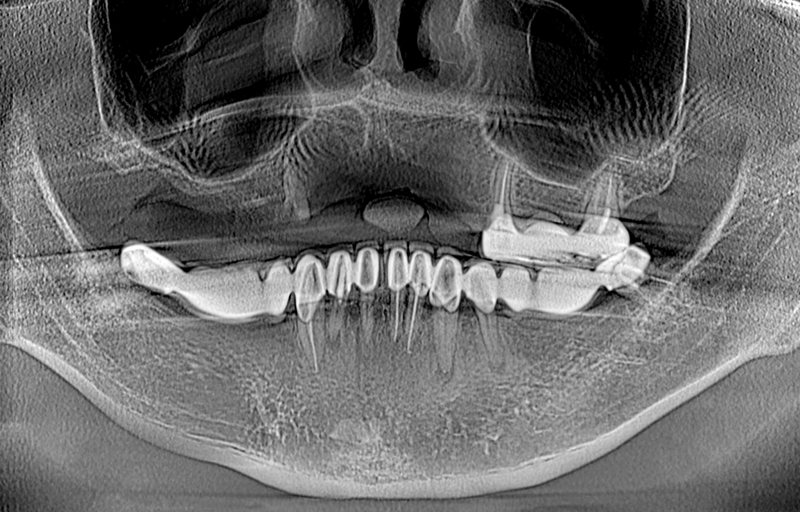

Cách tốt nhất chính là đến trực tiếp cơ sở bệnh viện nha khoa để được bác sĩ chẩn đoán và chụp phim CT để có thể xác định được chính xác tình trạng xương và đưa ra được phương pháp điều trị bệnh phù hợp nhất.